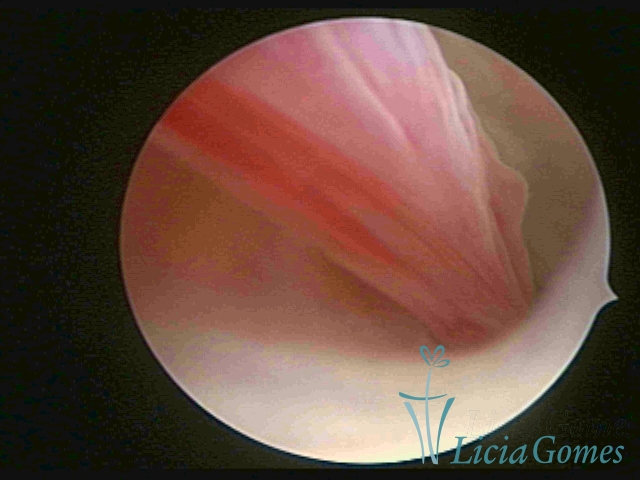

PÓLIPOS ENDOCERVICAIS

São tumores benignos, resultantes da proliferação focal reativa aos processos inflamatórios ou à situações de hiperestrogenismo, e podem ter sésseis (com a base de implantação larga) ou pediculados do epitélio.